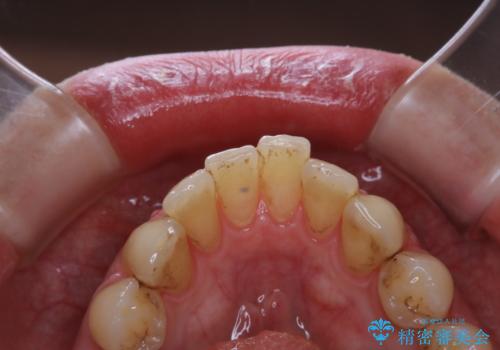

- かなり久しぶりの来院とのことで、クリーニング希望でした。全体的に汚れの付着があったため、PMTCの60分コースを行いました。

PMTCとは、プロフェッショナル・メカニカル・トゥース・クリーニングという、専門家による機械的な歯のクリーニングです。 PMTCは、歯磨きだけでは落とすことのできない細菌・バイオフィルムを除去することが目的です。

バイオフィルムとは、細菌の塊で、プラークの強固な集合体です。

バイオフィルムは、虫歯や歯周病の原因となります。